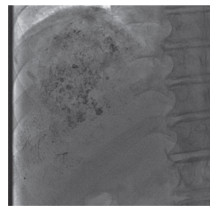

1.2 治疗方法休克患者需给予抗休克、补液等治疗,同时行急诊TAE手术。手术全程监测患者血压、血氧饱和度等情况。常规消毒、铺巾、2%利多卡因局部麻醉后,采用改良Seldinger技术穿刺股动脉,5F肝动脉导管插管至腹腔干造影,了解肝内肿瘤发生的部位、大小及供血动脉情况(图 1),同时观察有无伴有肝动静脉、门静脉瘘等情况。腹腔干造影时肝脏出现供血缺损区则需同时行肠系膜上动脉造影,仍有缺损区则继续寻找肝外供血动脉,动脉造影确诊后在肝左、右动脉或肝外供血动脉内使用微导管超选择性插管至肿瘤各支供血动脉。肝动脉造影显示造影剂外溢时,首先快速向靶血管内注射少量明胶海绵颗粒,以减少血流量,然后用碘油和明胶海绵颗粒或PVA颗粒进行超选择性栓塞。如有肝动脉门静脉瘘时,首先用明胶海绵颗粒封堵瘘口后再行栓塞,即使是多发性肿瘤患者总碘油量也要控制在10 mL以下,腹胀严重者行经皮腹腔穿刺引流治疗。

| 图 1 TAE术前造影可见肿瘤染色,未见造影剂外溢 Fig.1 TAE preoperative angiography showed tumor staining and no contrast agent spillage |